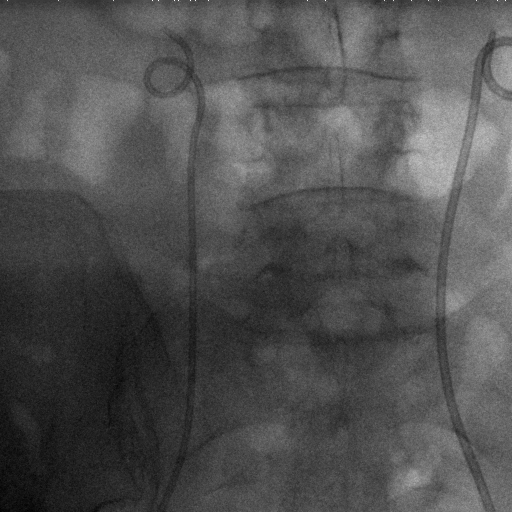

The dataset we use in the experiments is a cone-beam CT (CBCT) dataset captured for radiation therapy. The dataset contains 340 raw CBCT scans with each has 780 X-ray images. Each X-ray image comes with a geometry file that provides the registration ground truth as well as the information to reconstruct the CBCT volume. Each CBCT volume is reconstructed from the 780 X-ray images, and in total, we have 340 CBCT volumes (one for each CBCT scan). We use 300 scans for training and validation, and 40 scans for testing. The size of the CBCT volumes is 448×448×768448448768448\times 448\times 768 with 0.5 mm voxel spacing, and the size of the X-ray images is 512×512512512512\times 512 with 0.388 mm pixel spacing. During the experiments, the CBCT volumes are treated as the 3D pre-intervention data, and the corresponding X-ray images are treated as the 2D intra-intervention data. Sample X-ray images from our dataset are shown in Figure. Note that unlike many existing approaches [15, 17, 25] that evaluate their methods on small datasets (typically about 10 scans) which are captured under relatively ideal scenarios, we use a significantly larger dataset with complex clinical settings, e.g., diverse field-of-views, surgical instruments/implants, various image contrast and quality, etc.

We consider two common views during the experiment: the anterior-posterior view and the lateral view. Hence, only X-rays that are close to (±5°plus-or-minus5°\pm 5\degree) these views are used for training and testing. Note that this selection does not tightly constrain the diversity of the X-rays as the patient may be subject to movements with regard to the operating bed. To train the proposed method, X-ray and DRR pairs are selected and generated with a maximum of 10°10°10\degree rotation offset and 202020 mm translation offset. We first invert all the raw X-ray images and then apply histogram equalization to both the inverted X-ray images and DRRs to facilitate the similarity measurement. For each of the scan, we also annotate their landmarks on the reconstructed CBCT volume for further evaluation.

Refer to caption

Figure 6: Sample raw X-ray images of our dataset.